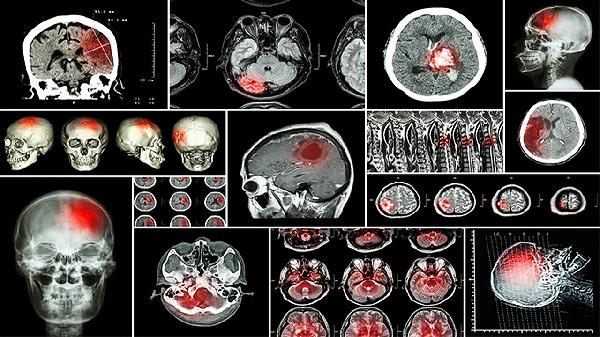

甲癌复发的时间通常在术后1-3年内,但具体时间因人而异,需根据患者病情和治疗情况综合评估。甲癌复发的原因包括手术切除不彻底、肿瘤恶性程度高、术后未规范治疗等。治疗上需根据复发部位和病情选择手术、放疗、碘-131治疗或靶向治疗等方案,同时结合定期随访和健康管理。

1、甲癌复发的时间受多种因素影响。术后1-3年是复发高峰期,尤其是恶性程度较高的甲状腺癌,如未分化癌或髓样癌。低风险患者复发率较低,但仍需长期监测。复发时间也与术后治疗是否规范有关,如未进行碘-131治疗或未按时服药,复发风险可能增加。

3、肿瘤恶性程度高是复发的另一重要因素。甲状腺癌分为分化型、髓样型和未分化型,分化型如乳头状癌和滤泡状癌复发率较低,而髓样癌和未分化癌复发率较高。肿瘤大小、是否侵犯周围组织及血管也影响复发风险。病理检查结果可帮助评估肿瘤恶性程度。